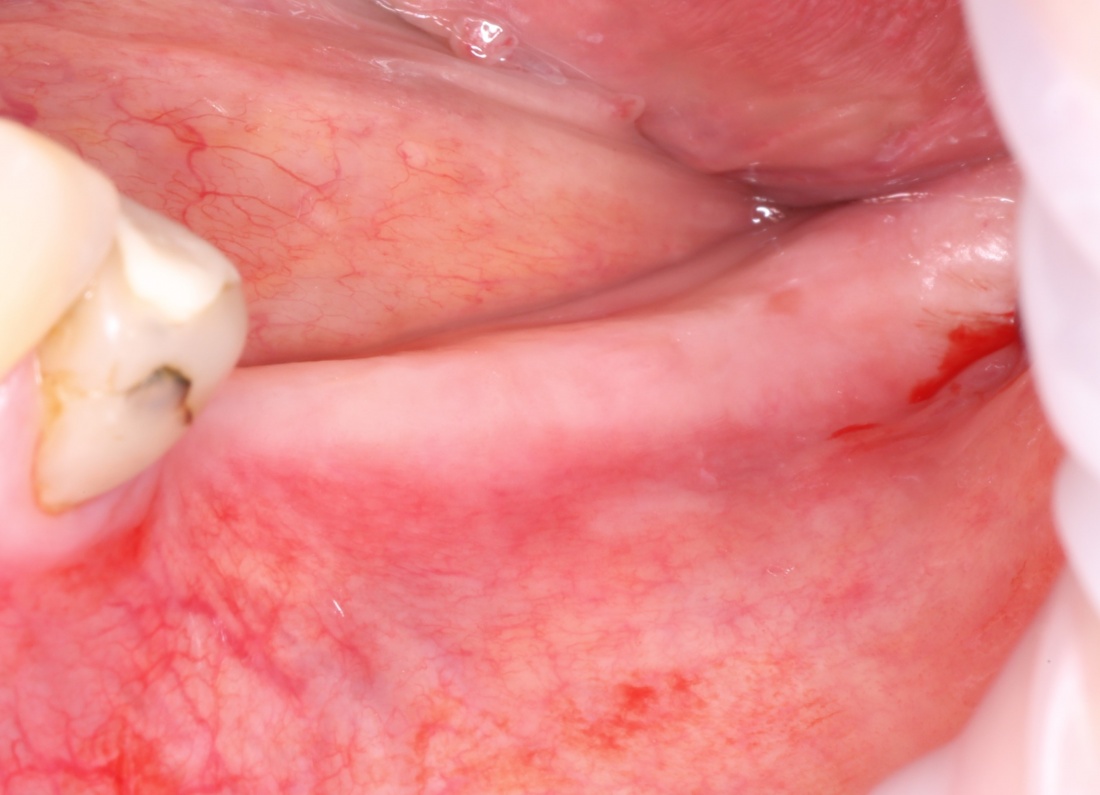

Простой. Надежный. Дешевый. Способ остеопластики.